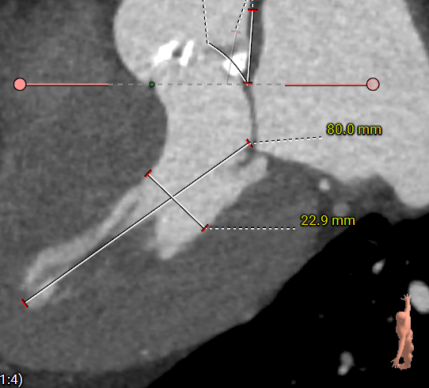

主动脉根部评估

主动脉瓣瓣环周长65.0mm,平均周长径 20.5mm,sov:25.7mm*27.1mm,瓣叶增厚,钙化主要分布于瓣叶,瓣环水平夹角51°。

冠脉高度测量

左冠开口高度10.6mm

右冠开口高12.0mm